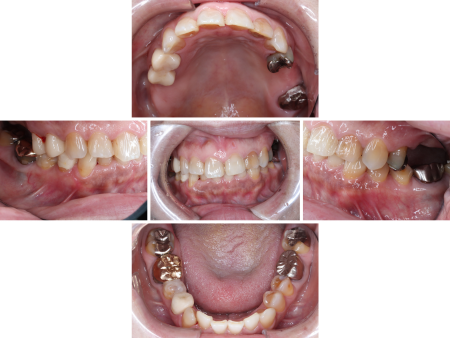

「左上奥歯に痛みがあり、歯ぐきも腫れている。右上の部分入れ歯もあまりよく噛めない。他院にて痛みや腫れを相談したところ様子を見るように言われたが、なかなか治らないため診てほしい」とお困りの様子で、当院のホームページを見てご来院いただきました。

拝見したところ、左上奥歯(第1大臼歯 /6番)が欠損しており、前後の歯を削って橋渡しのように被せ物を入れる「ブリッジ」で補っていました。

ブリッジを支えている手前の歯(第2小臼歯/5番)の歯ぐきに腫れや痛みがあり、これは歯ぐきや歯を支える骨が細菌感染したことが原因と考えられます。

症状がかなり進行していたため治療しても残すことが難しく、残念ながら抜歯が必要と診断しました。

また、銀歯が入っている左上の歯2本(第1小臼歯/4番、第2大臼歯/7番)は内部で虫歯が再発しており、歯を温存するためには虫歯の再治療が必要です。

右上奥歯2本(第1大臼歯、第2大臼歯)の欠損部位は部分的な入れ歯で補っていますが、入れ歯が合っていないためしっかり噛めていませんでした。